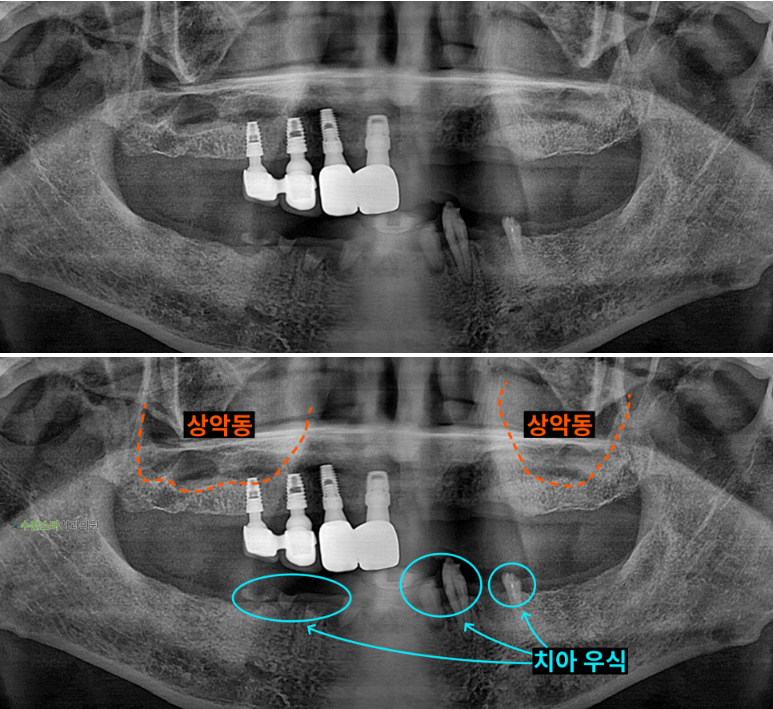

내원 시 파노라마

처음 내원 시 파노라마, 70대 남성 (2025.9 촬영)

내원 시 파노라마 사진입니다.

환자분께서 상악은 부분 틀니,

하악은 전체 틀니를

사용하셨으나

틀니의 이물감과 압박감이 심해

식사와 일상생활에서

큰 불편함을 느끼셨다고 합니다.

하늘색 표시 부분을 보면

하악은 충치로 인해서

치아가 썩어 있습니다.

타 치과에서 상악 오른쪽에

임플란트 시술과

발치를 진행하고,

새 틀니를 제작하신 지

얼마 되지 않은 상태였습니다.